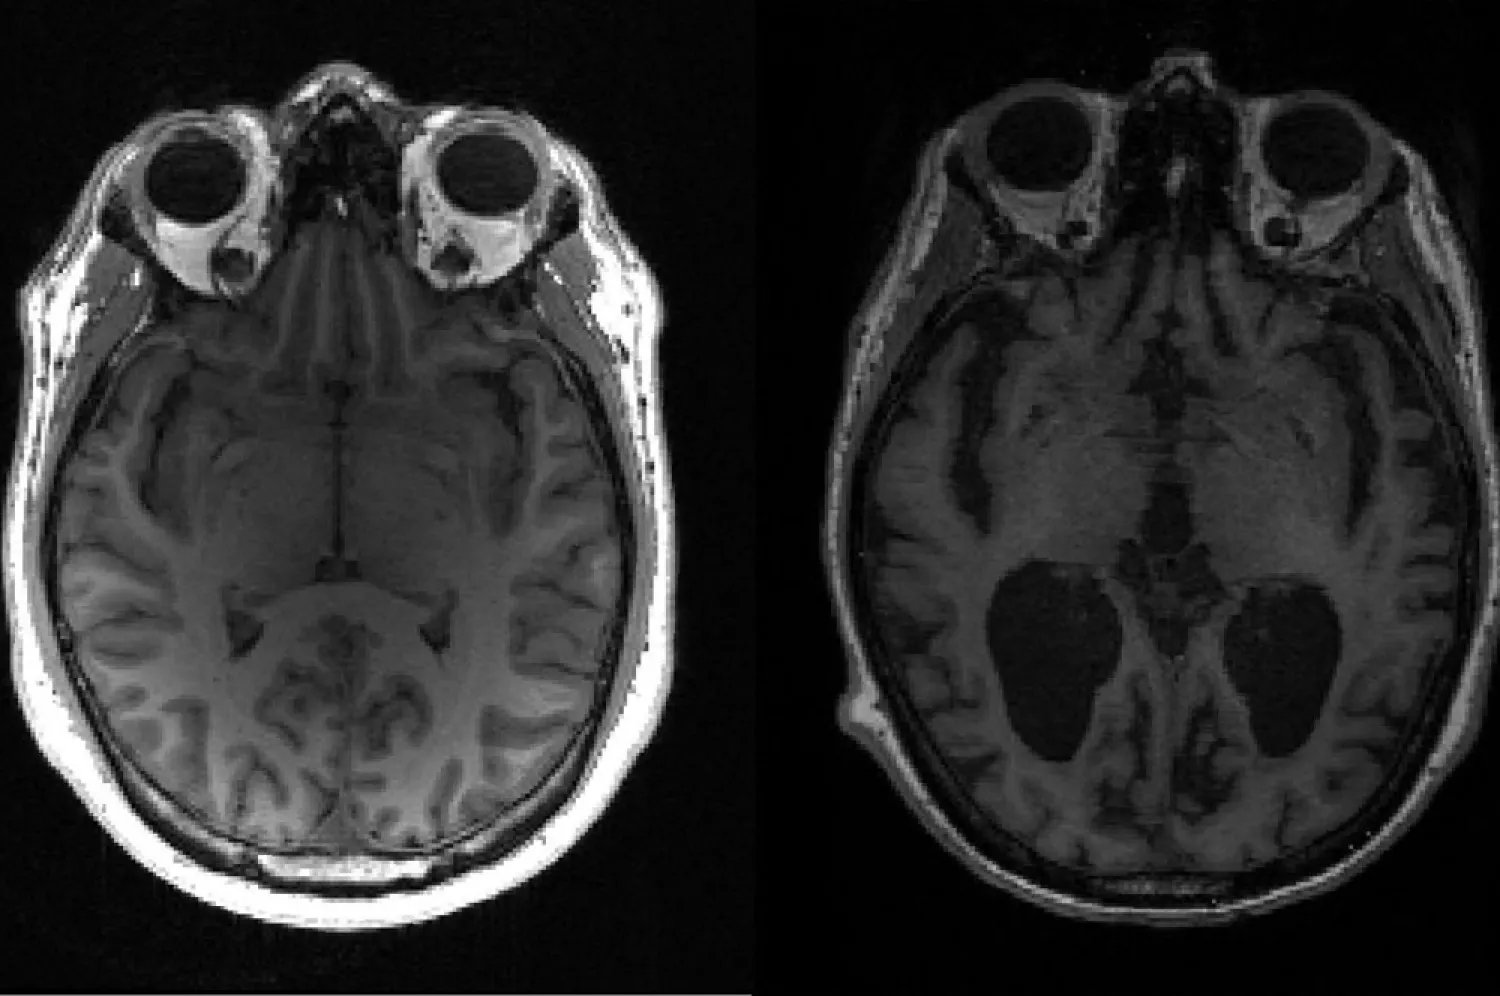

This undated image courtesy of, Dr. Timothy Rittman, University of Cambridge, shows an MRI image of a healthy brain (L) and an Alzheimer's brain (R) with large black gaps where brain has shrunk. (AFP)